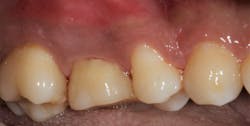

Root amputation remains a viable treatment to save maxillary molars and can have long-term success rates equal to dental implant therapy (figures 9 and 10).Editor’s note: This article originally appeared in Perio-Implant Advisory, a chairside resource for dentists and hygienists that focuses on periodontal- and implant-related issues. Read more articles and subscribe to the newsletter.